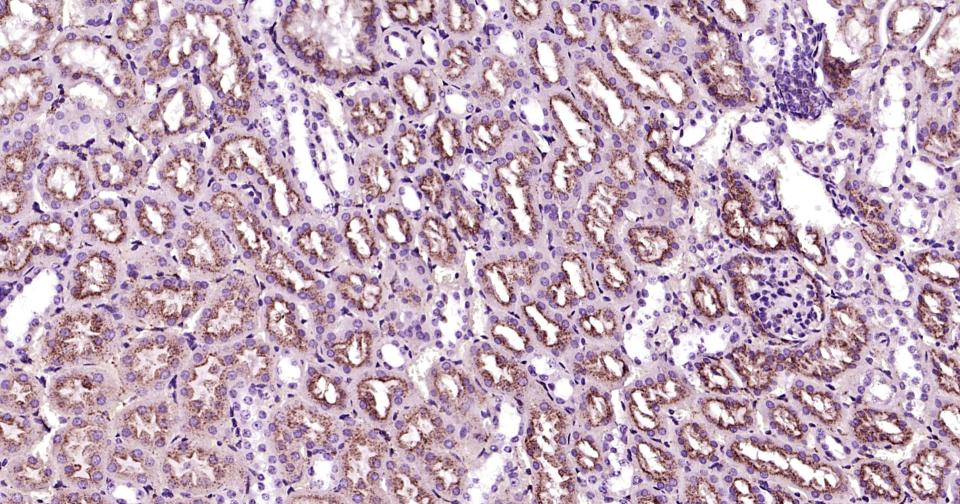

Paraformaldehyde-fixed, paraffin embedded Human kidney;Antigen retrieval by boiling in sodium citrate buffer (pH6.0) for 15 min; Antibody incubation with LAMP2 Monoclonal Antibody, Unconjugated (bsm-61207R) at 1:200 overnight at 4°C, followed by conjugation to the bs-0295G-HRP and DAB (C-0010) staining.